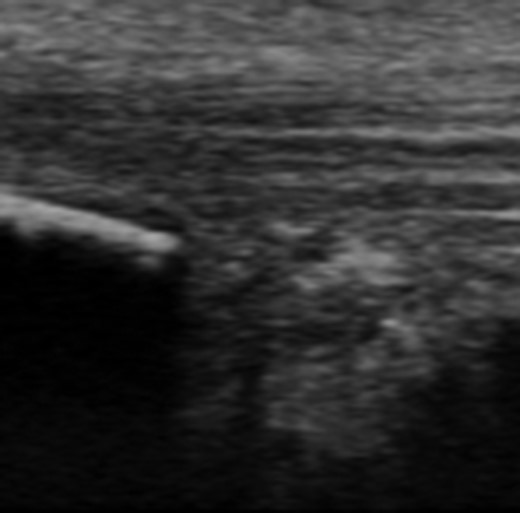

Dynamic ultrasound examination of the left heel showed a diffusely thickened subcutaneous bursa, with fluid-rich islands. Regions of high blood flow were seen in the bursal walls. There was tendinopathy in the distal Achilles, which measured 6–7 mm in thickness with intra-tendinous bone formations and calcification, but no high blood flow. Finally, there was a minor Haglund-like deformity with a sharp edge and a slightly enlarged retrocalcaneal bursa with the appearances of scar tissue formation, but no fluid or increased blood flow. There were no signs of partial ruptures in the distal part of the Achilles. These ultrasound findings were consistent with those of a previous MRI (Figs 1–5).

Ultrasound image of diffusely thickened subcutaneous bursa and underlying intra-tendinous bone formations.

Ultrasound image of minor Haglund deformity with sharp edge. Enlarged retrocalcaneal bursa with appearance of bursal scar tissue formation.